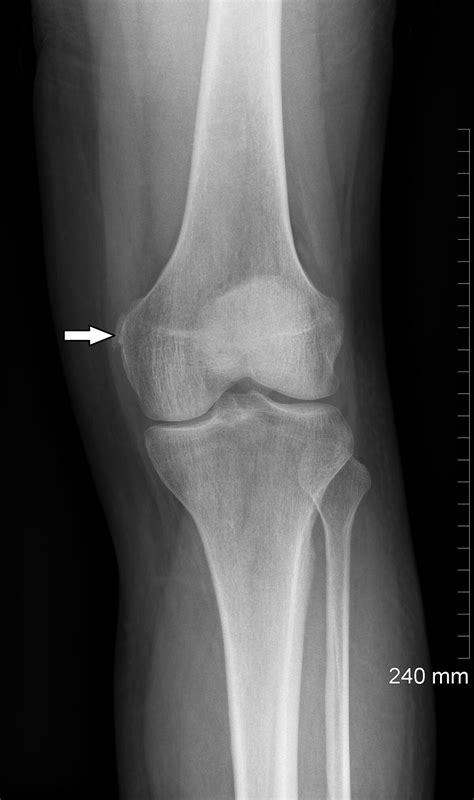

A Pellegrini Stieda Lesion is a rare condition characterized by the calcification of the medial collateral ligament (MCL) of the knee. The MCL is a crucial ligament that provides stability to the inner side of the knee joint. When this ligament becomes calcified, it can lead to pain, stiffness, and reduced range of motion. The condition is named after the Italian surgeon Pellegrini and the German surgeon Stieda, who first described it in the late 19th century.

• Imaging Tests: X-rays, ultrasound, or MRI scans to visualize the calcification and assess the extent of the damage.

• pellegrini stieda lesion xray

• pellegrini stieda calcification